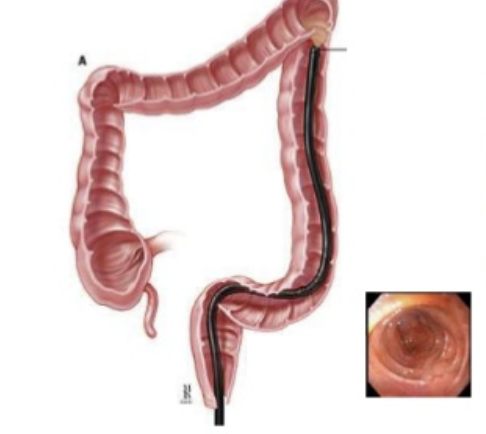

Colonoscopy

visualize the entire colon looking for polyps, malignancy, diverticulitis, requires full sedation and cleanout